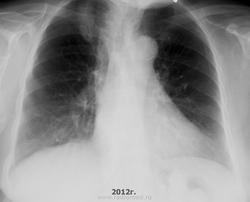

Насчет случая давайтей разбираться. Имеется прогрессирование между 2008 и 2009 г. - это видно. Причем старый фиброзный очаг есть в 1 м.р. справа и петрификаты слева, а теневая картина нарастает в проекции 1 ребра справа. На боковой проекции патология видна предположительно. Сама тень в последнем наблюдении формируется по типу инфильтрата с нечеткими контурами, преимущественно перибронхиально, "соосно" верхнедолевому бронхо-сосудистому пучку. При этом видны просветы бронхов, входящих в инфильтрат.

Хммм для туберкулеза не думаю что характерная картина. С учетом того что аорта склерозирована и сглажена талия сердца и видно что это человек в возрасте старше 30 лет то я бы стал искать сначала рачок вместо ТБС

Из сказаннного можно предположить, что по представленным снимкам, аргументированно вынести заключение о БАР не представлялось возможны, НО ретоспективно проведя анализ, можно было предположить, что имели дело с БАР ( профессор Власов П.В.( к сожалению, ныне покойный), говорил, что если на R-грамме лёгких изменения ни на что не похожи- думай о БАР).

Как-то слово "обострение" тут плоховато звучит. Это же не язва и не хронический холецистит. Реактивация ну или прогрессирование подошло бы лучше. Хотя и признаков сего здесь тоже не было. Свежих ("мягких") очагов не появилось, отсевов тоже не было, реакции плевры и выпотов аналогично. Даже если был туберкульоз в анамнезе, данная скиалогическая динамика, как по мне, не вписывается в тубпроцес. Имея на руках все снимки стоило в первую очередь подумать про рак. Рентгенолога особо винить не стоит. Как говорил один старый академик-фтизиатр - туберкульоз и рак в первых сегментах часто ходят под руку.